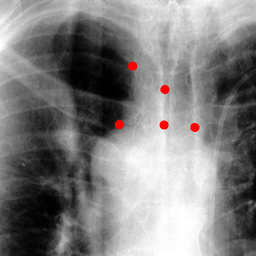

Shift-Invariant Tracking. The POINT network benefits from the shift invariant property of the convolution operation, which makes it less sensitive to the in-plane offset of the DRRs. Figure 8 shows some tracking results from the POINT network. Here the odd rows show the (a) X-ray and (b-d) DRR images. The heatmap below each DRR shows the tracking result between this DRR and the leftmost X-ray image. The red and the blue marks on the X-ray and DRR images denote the POIs. The red and the blue marks on the heatmaps are the ground truth POIs and the tracked POIs, respectively. The green blobs are the heatmap responses and they are used to generate the tracked POIs (blue) according to Equation (7). The numbers under each DRR denote the mPD scores before and after the tracking. As we can observe that the tracking results are consistently good, no matter how much initial offset there is between the DRR and the X-ray image. This shows that our POINT network indeed benefits from the POI convolution layer and provide more consistent outputs regardless of the in-plane offsets.

Refer to caption

(a)

(b) 13.6 \rightarrow 7.3

(c) 22.9 \rightarrow 9.0

(d) 37.1 \rightarrow 7.8

(e)

(f) 19.5 \rightarrow 8.7

(g) 26.0 \rightarrow 9.5

(h) 41.1 \rightarrow 11.4

(b)

(c)

(d)

Figure 8: POI tracking results. (a) X-ray image. (b-d) DRR images with different in-plane offsets. The heatmaps of the tracking results are all aligned with the X-ray images and appear similar, showing the shift-invariant property.